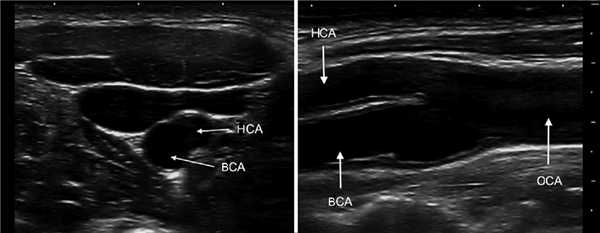

В В-режиме и ЦДК сканируют ОСА до бифуркации; выше бифуркации исследуют НСА через передний доступ, ВСА через боковой доступ.

Для исследования ОСА датчик располагают вдоль наружного или внутреннего края кивательной мышцы. ОСА оценивают на всем протяжении от устья до бифуркации.

У основания шеи кнутри от ОСА щитовидная железа, кнаружи — внутренняя яремная вена. Под давлением датчика ВЯВ сжимается, а ОСА нет.

От основания шеи перемещайте датчик вверх к бифуркации ОСА — место деления на НСА и ВСА. Здесь небольшое расширение — луковица.

У бифуркации ОСА расширение луковицы, начинается голый ствол ВСА и ветвящаяся НСА. Первая ветвь НСА — верхняя щитовидная артерия.

На уровне бифуркации ВСА шире НСА; расположена кнаружи и кзади от НСА, выше перемещается кнутри; не имеет ветвей на шее.